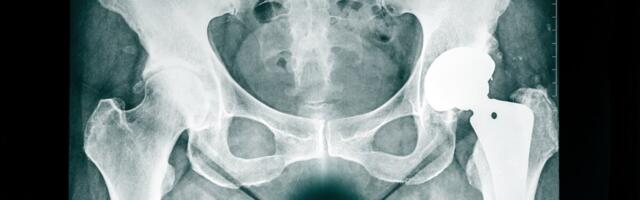

Läti patsientidel 2-3aastane ootejärjekord endoproteesimisele

Läti riiklik süsteem lubab aastas vaid 111 endoproteesioperatsiooni, kuid järjekorras ootab 300 patsienti, tekitades kuni kolmeaastase ootejärjekorra.